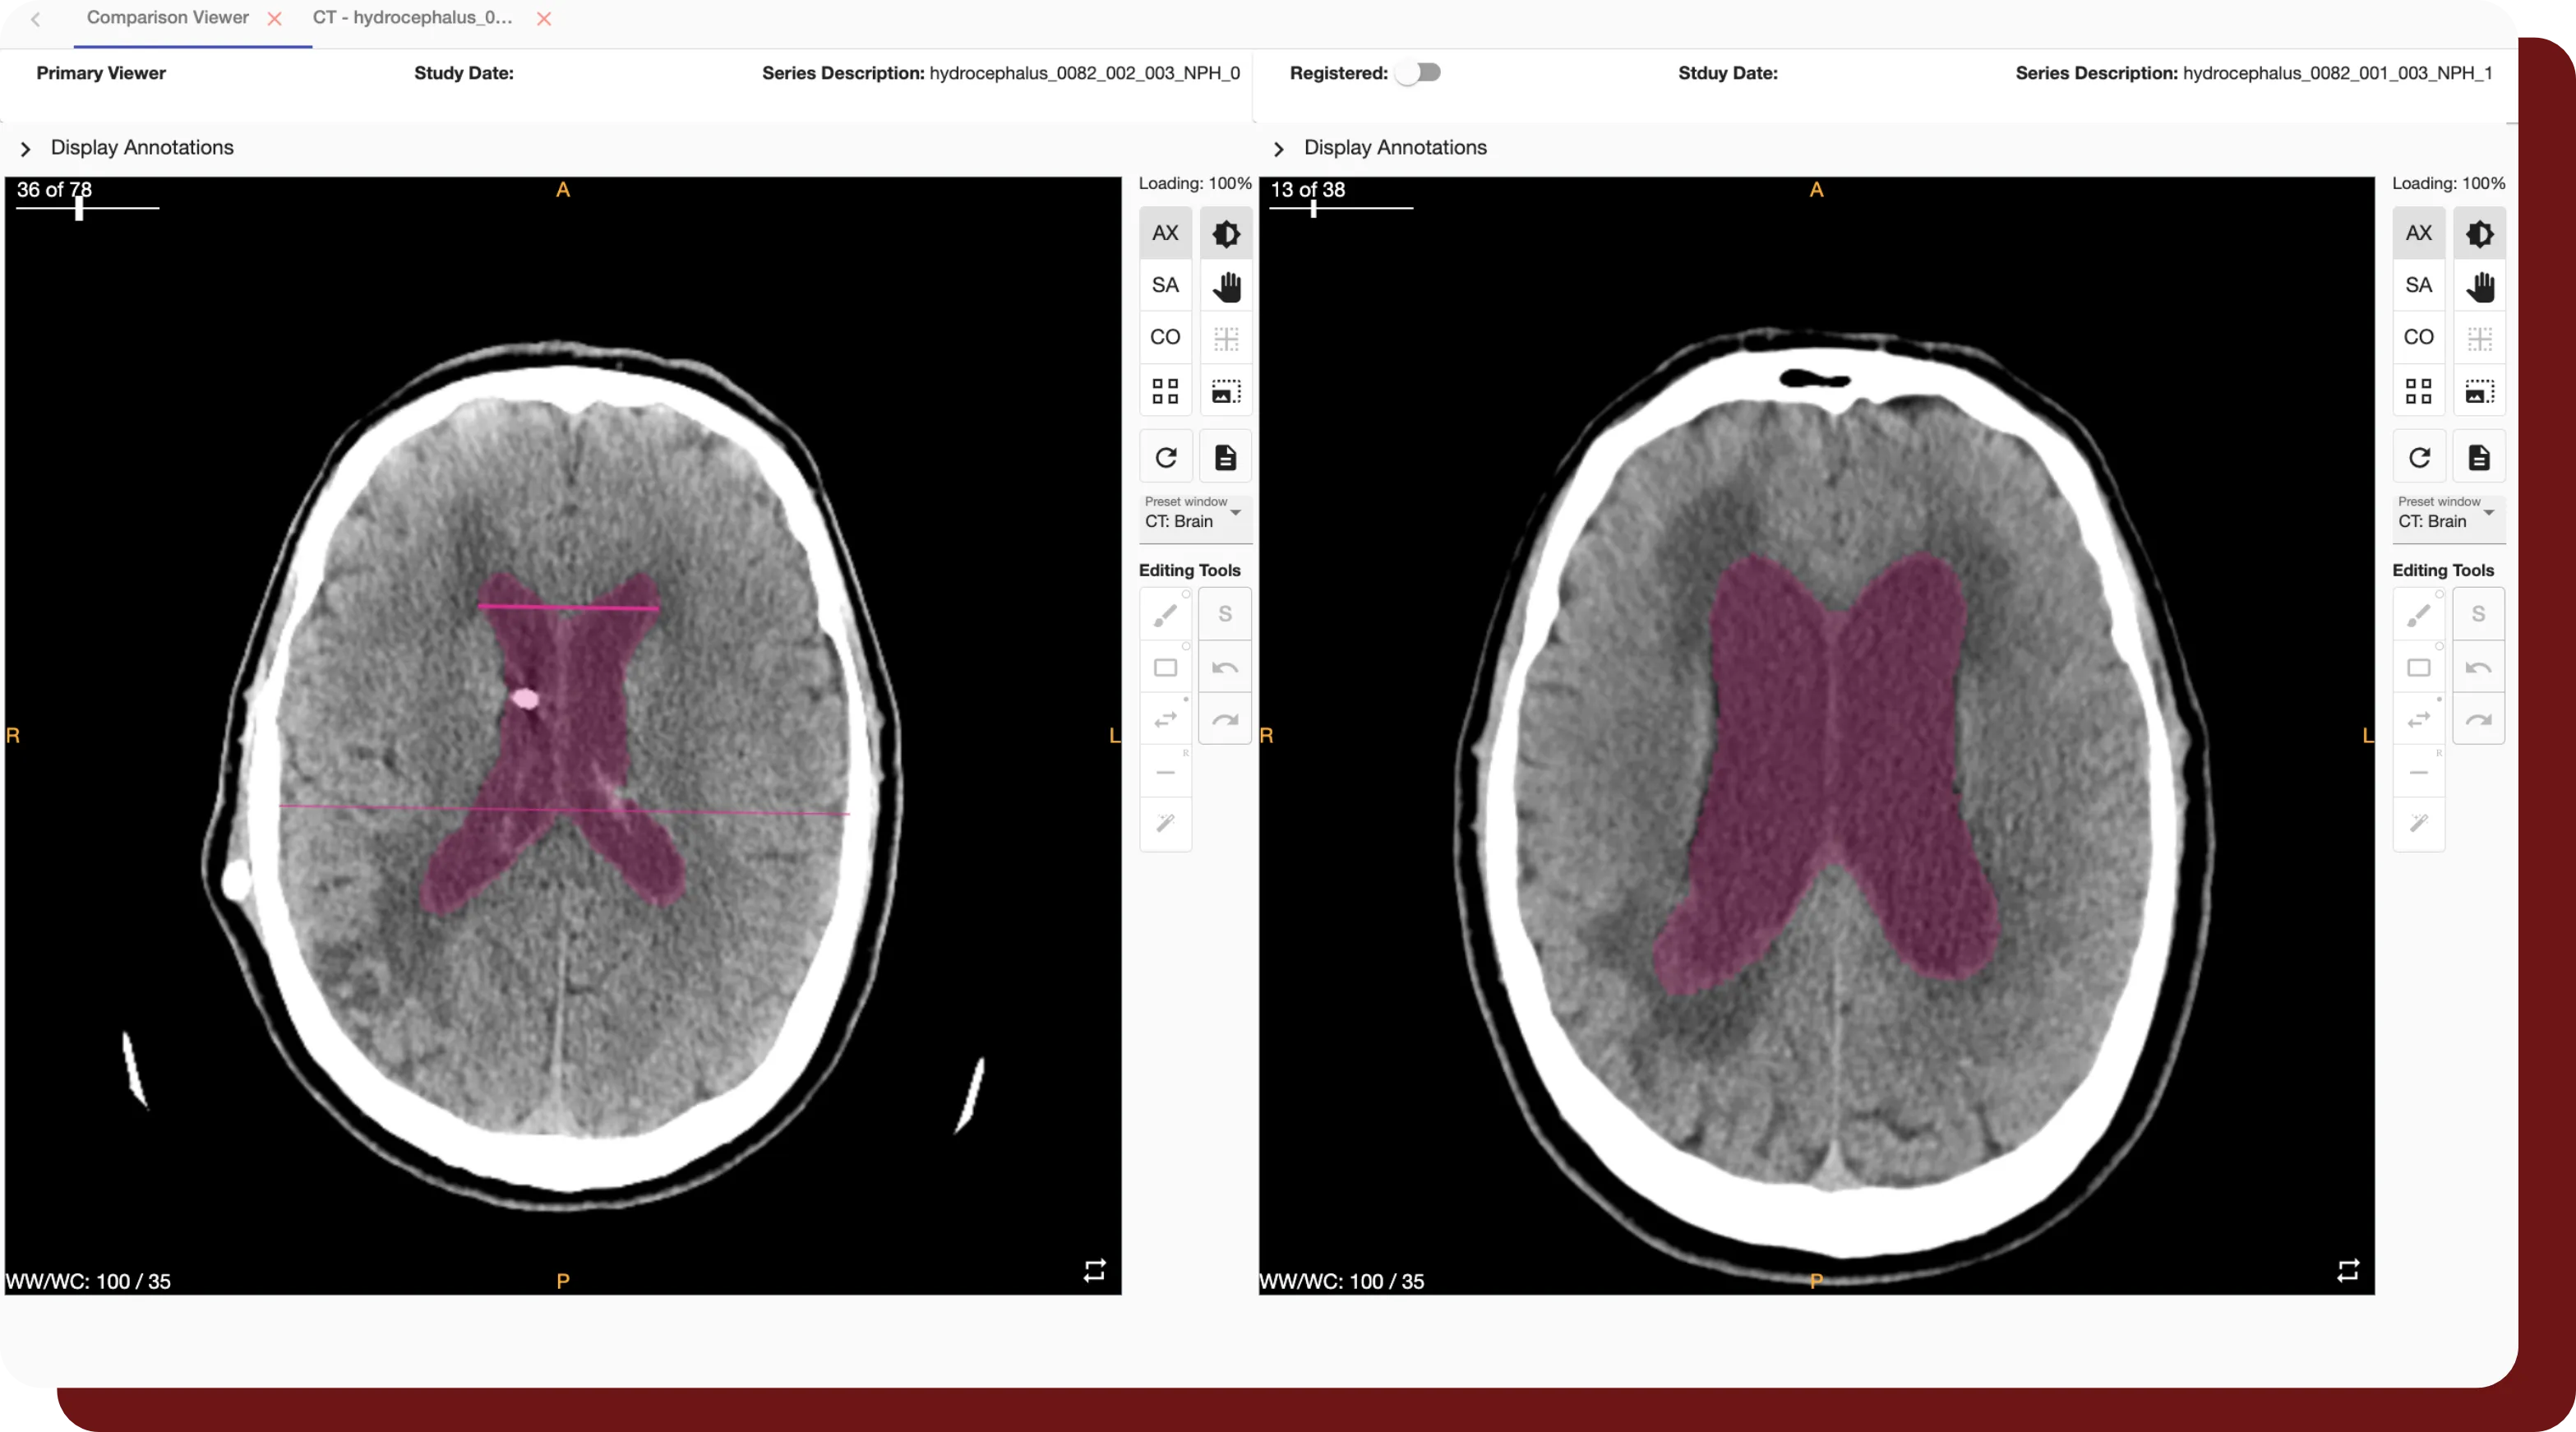

An example of the Comparison Viewer feature available in QuantBrain - Ventricle.

Longitudinal Tracking

• QuantBrain - Ventricle enables longitudinal analysis across series in order to track changes over time.